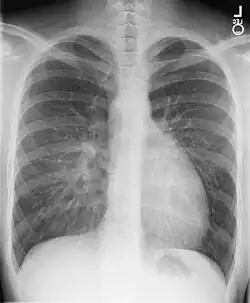

La transposición de los grandes vasos (TGV), son un grupo de defectos congénitos del corazón en la que se presenta una disposición anormal de los principales vasos sanguíneos que salen y entran al corazón: la vena cava superior y/o la inferior, la arteria pulmonar, las venas pulmonares y la aorta. Si solo se afectan las arterias (arteria pulmonar y aorta), el trastorno se conoce como transposición de las grandes arterias. La transposición de los grandes vasos fue descrita por primera vez en 1797 por Matthew Baillie.[1]